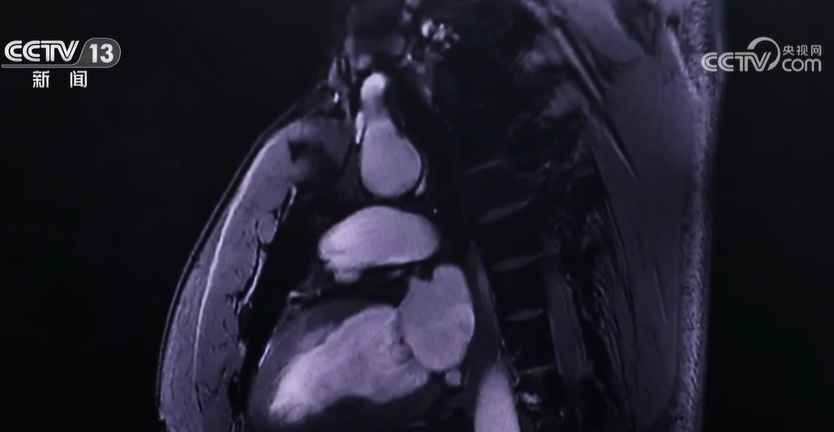

总台记者 朱慧容:在分辨率不是很高的核磁共振机器做出来的情况下,看不出来具体的病灶在哪里。但是在这个分辨率很高的核磁共振提供的影像上,就明显地看出,这里可能是一个肿瘤的所在位置。

记者了解到,这款仪器可以获得人体的全身影像,不仅分辨率更高,还加速了成像速度。